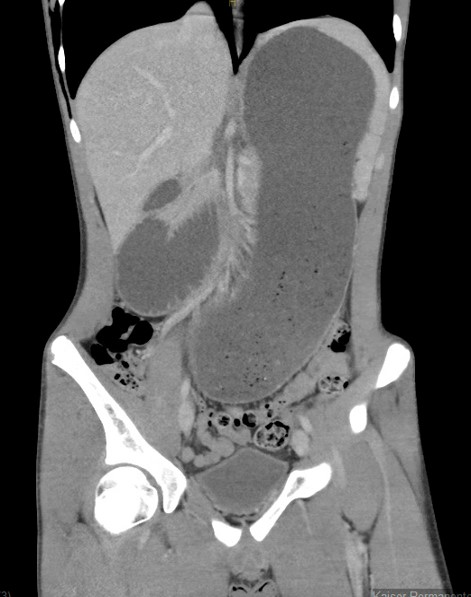

Computed tomography downloaded from Occupational Safety and Health

CT Scan

YouTube link for the initial CT scan is available at https://youtu.be/jG0J2b3EhhU.

Impression

Extensive air surrounded the esophagus and within the mediastinum, with dissecting along soft tissue planes, as described, suggestive of an esophageal perforation.

There is no free air in the abdomen. There is dilated stomach and proximal duodenum, with narrowing of the duodenum as it crosses the superior mesenteric artery (SMA). This can be seen with SMA syndrome in the proper clinical setting.